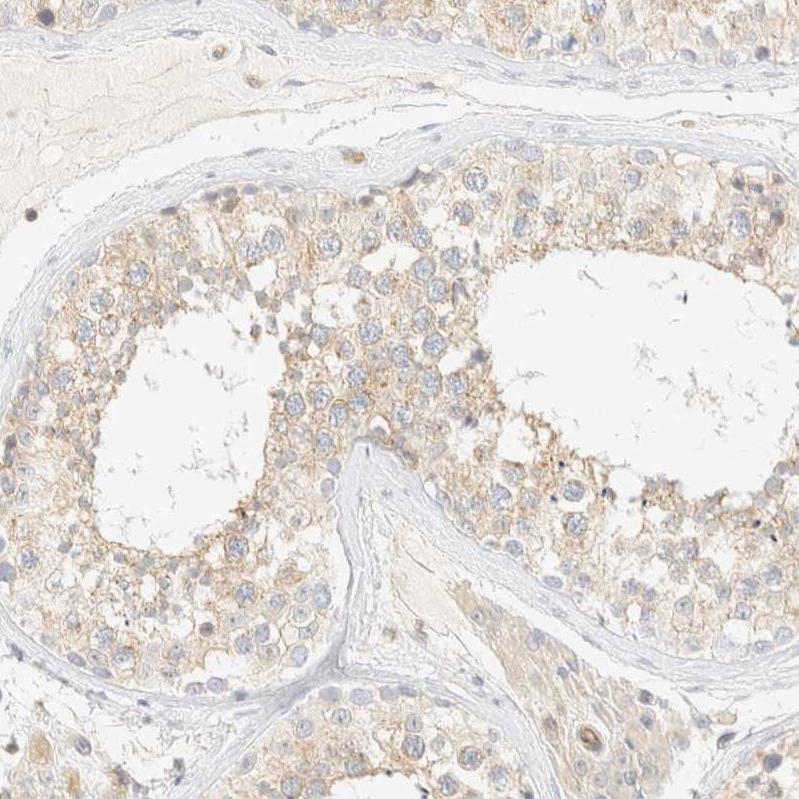

Immunohistochemical staining of human colon shows moderate cytoplasmic positivity in glandular cells.